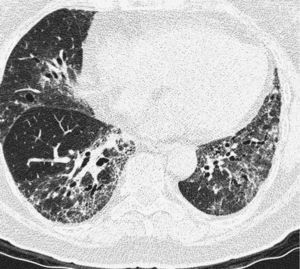

Pulmonary manifestations can be an extraglandular complication, with reported prevalence varying widely (9–75%), depending on the methods of detection and patient selection. Lung involvement (symptoms and either pulmonary function testing or radiographic abnormalities) can occur in 10–20% of patients.2 Image techniques, such as chest radiographs and high resolution computerized tomography (HRCT), are the most useful tools to detect lung involvement. A plain chest X-ray has a low sensitivity to detect early lung involvement. Studies that systematically perform HRCTs, even in asymptomatic patients, report higher rates of pulmonary abnormalities compared with studies based on clinical symptoms.3 HRCT may identify ground-glass attenuation, thin-walled cysts, honeycombing, reticular pattern, small nodules and enlarged mediastinal lymph nodes. Several histopathologic patterns have been described in PSS, including nonspecific interstitial pneumonia (NSIP), usual interstitial pneumonia (UIP), organizing pneumonia (OP) and lymphocytic interstitial pneumonia (LIP). Most of these patterns are known as diffuse interstitial lung disease (ILD). LIP has a typical radiographic appearance in ground glass opacities with thin-walled cysts, and the presence of these cysts on HRCT scan should raise clinical suspicion for PSS with ILD.4,5

NSIP is the most commonly observed histopathological pattern in connective tissue diseases with ILD, including PSS. In patients with PSS and ILD, HRCT and histopathological findings are well correlated6 and a lung biopsy is usually not recommended. However, radiographic features suggestive of lymphoma (consolidation, large nodules or pleural effusions) require thorough investigation7 (Figs. 1–3).